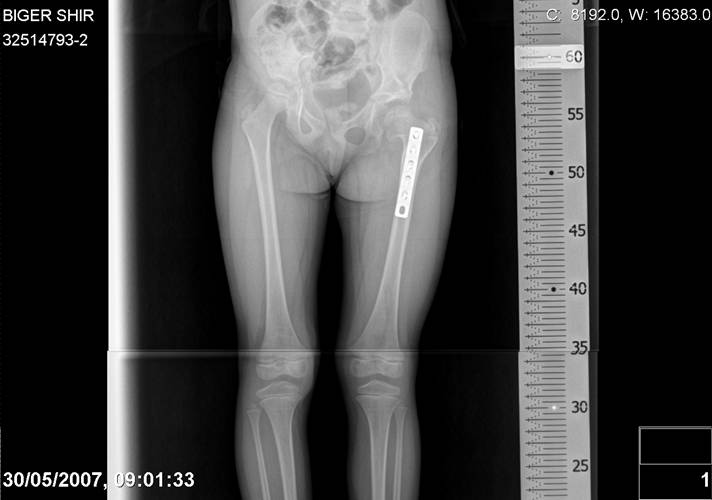

Navernoe Dega

Chto by ne byt goloslovnym posilau vam svoi sluchai gde sdelal vse chto napisal vyshe

Mark Eidelman